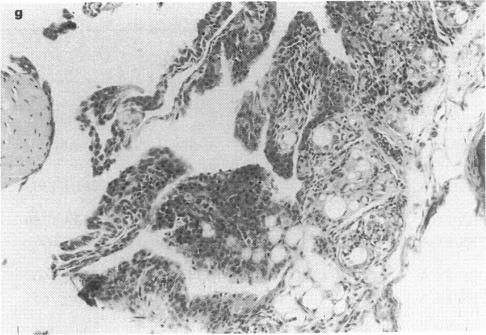

Adjuvant arthritis, induced by injections of Freund's complete adjuvant into the footpads of some rat strains, has been recognized as a useful animal model for many years. There has, however, been notable lack of success in reproducing this model in other species. We now describe the development of adjuvant arthritis in healthy strain mice approximately 2 months after injection of Freund's complete adjuvant. Although the clinical appearance of the mice and the joint histopathology closely resemble the adjuvant arthritis reported in the rat, we were unable to detect rheumatoid factor in sera from the affected animals. In parallel studies of T cell proliferation, affected animals responded to some mycobacterial antigens but not to the 65-kD heat shock protein of Mycobacterium tuberculosis, suggesting that some other epitope is important in the development of the disease.

多年来,通过向某些大鼠品系的足垫注射弗氏完全佐剂诱导的佐剂性关节炎,一直被认为是一种有用的动物模型。然而,在其他物种中复制该模型一直未取得显著成功。我们现在描述在健康品系小鼠中注射弗氏完全佐剂约2个月后佐剂性关节炎的发展情况。尽管小鼠的临床表现和关节组织病理学与大鼠中报道的佐剂性关节炎非常相似,但我们无法在患病动物的血清中检测到类风湿因子。在T细胞增殖的平行研究中,患病动物对一些分枝杆菌抗原有反应,但对结核分枝杆菌的65-kD热休克蛋白无反应,这表明其他一些表位在该疾病的发展中很重要。